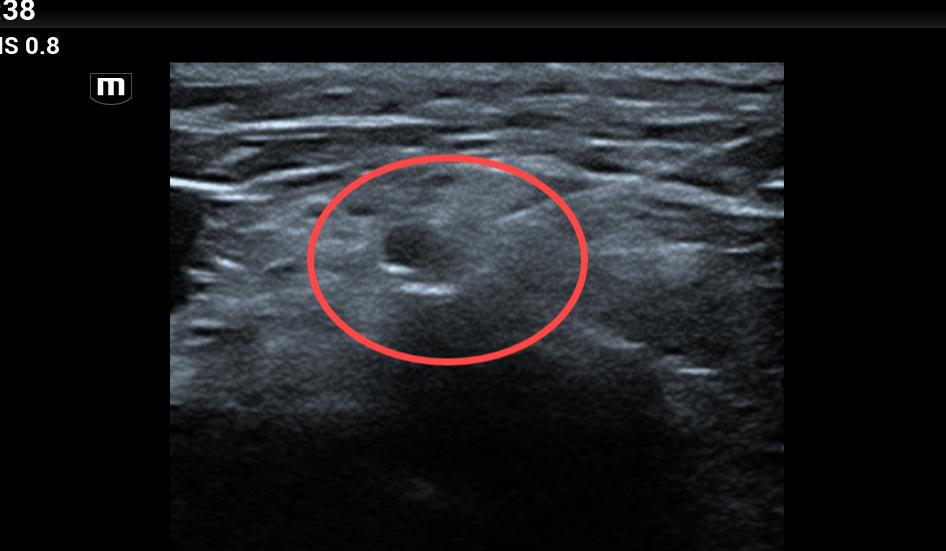

在充分了解患者既往病史并征得患者及家属同意后,麻醉科专家团队为患者制定了经皮穿刺超声引导下神经射频消融术治疗方案,以低频超声探头逐级引导穿刺到腋腭窝处,通过0.8HZ,脉宽300ms,温度42℃的射频脉冲模式为患者进行治疗,经过3个周期(3分钟/周期)的治疗,患者表示疼痛明显缓解;在术中,患者无明显的不适,几乎无出血。

(二)超声引导与C臂、DSA、CT引导相比较,具有移动方便、价格便宜、无辐射等优点,可实时观察穿刺针位置,清楚识别到靶点周围重要组织,避免不良反应的发生。